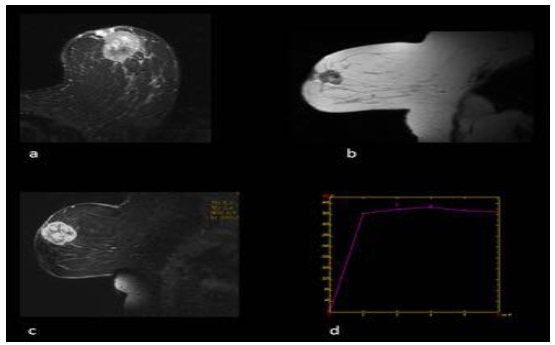

Características en RNM del CMTN

En los resultados de las características en resonancia magnética, se debe tener en cuenta que de las 17 pacientes solo se dispone información de 8 resonancias magnéticas realizadas en centros periféricos. Esto representa el 75% de la muestra, equivalente a 8 casos.

De estos casos se destaca que informan una cantidad de tejido fibroglandular tipo B, aunque no describen el realce parenquimatoso de fondo ni hallazgos asociados.

En lo que respecta a la descripción nodular, se encontró que en el 77,7% de los casos (7 de 8) el nódulo se reportó como redondeado, seguido de la forma ovalada.

Los márgenes del nódulo en 7 casos se describen como circunscritos y solo en 1 caso se reporta como espiculado.

Según lo referido realce interno del nódulo, 5 casos presentaron realce heterogéneo periférico y 3 casos mostraron un realce en forma de anillo.

Finalmente, en la evaluación de la valoración de las curvas cinéticas, se notó que en la fase inicial los 8 casos tenían una fase rápida. En la fase tardía, 6 de los casos presentaban un patrón de wash out, mientras que 2 casos mostraban un tipo de realce en meseta.

Los resultados de resonancia magnética mostraron hallazgos consistentes con la literatura, incluyendo el realce periférico, nódulos heterogéneos y curvas cinéticas tipo 2 y 3. A pesar de la limitada disponibilidad de resonancias magnéticas en centros periféricos, estos hallazgos respaldan la utilidad de esta técnica en la evaluación de tumores mamarios.

Anexo 3. Imágenes CMTN en resonancia magnética